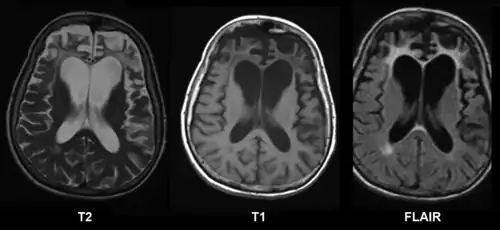

Há uma série de testes neuropsicológicos disponíveis para esclarecer a natureza e a extensão da disfunção do lobo frontal. Por exemplo, a formação de conceitos e a capacidade de mudar conjuntos mentais podem ser medidas com o Teste Wisconsin de Classificação de Cartas, e o planejamento pode ser avaliado com o subteste Labirintos do WISC [en].[3] A demência frontotemporal aparece como atrofia do córtex frontal na ressonância magnética.[21] O comprometimento frontal devido a lesões na cabeça, tumores ou doença cerebrovascular também aparecerá na imagem cerebral.[4]